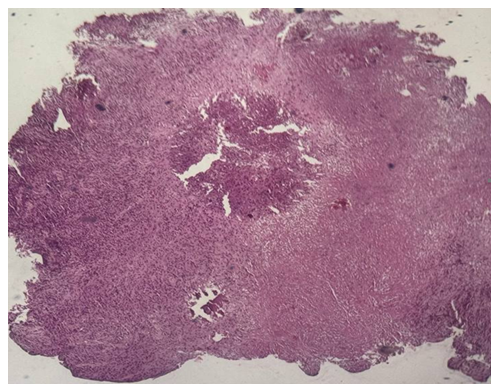

Tumor types and localizationHistopathological diagnoses comprised: Surgical specimens | Picture 1. Surgically resected specimen of salivary gland tumor. Histological appearance of adenocarcinoma, stage I, localized in the left parotid gland (3 cases; Nos. 849-b, 841-b, 482-b). The tumor shows irregular glandular and tubular structures lined by atypical epithelial cells with mild pleomorphism (H&E stain) |

| Picture 4. Surgically resected specimens of salivary gland tumors. Histological appearance of undifferentiated carcinoma (4 cases), localized in the right palatal mucosa (Nos. 1297, 1298) and mandible (Nos. 1383, 1384). The tumor is composed of solid sheets and nests of atypical epithelial cells with a high nuclear–cytoplasmic ratio, marked nuclear pleomorphism, hyperchromasia, and absence of glandular differentiation (H&E stain) |

Morphological description: Tumor tissue demonstrates a solid growth pattern with sheets of atypical epithelial cells. The cells show high nuclear-cytoplasmic ratio, hyperchromatic nuclei, and loss of normal glandular architecture. Areas of necrosis and irregular stromal infiltration are evident. No clear glandular or squamous differentiation is observed, which corresponds to the diagnosis of undifferentiated carcinoma. Figure 1. Histological section of undifferentiated carcinoma of the salivary gland showing solid sheets of atypical cells with hyperchromatic nuclei and absence of glandular differentiation (H&E stain, ×10). | Figure 2. Undifferentiated carcinoma (mandibular localization, H&E stain, ×10) |

Morphological description: The histological section demonstrates infiltrative tumor growth with dense sheets of atypical epithelial cells. Cells display pleomorphism, irregular nuclear contours, hyperchromasia, and scant cytoplasm. The stroma is fibrous, with focal desmoplastic reaction. No signs of glandular or squamous differentiation are present, which is consistent with the diagnosis of undifferentiated carcinoma of the mandible. Figure 2. Undifferentiated carcinoma of the mandible showing sheets of pleomorphic tumor cells with hyperchromatic nuclei and fibrous stromal reaction. No evidence of glandular or squamous differentiation is observed (H&E stain, ×10). | Figure 3. Monomorphic adenoma (left submandibular gland, H&E stain, ×20) |